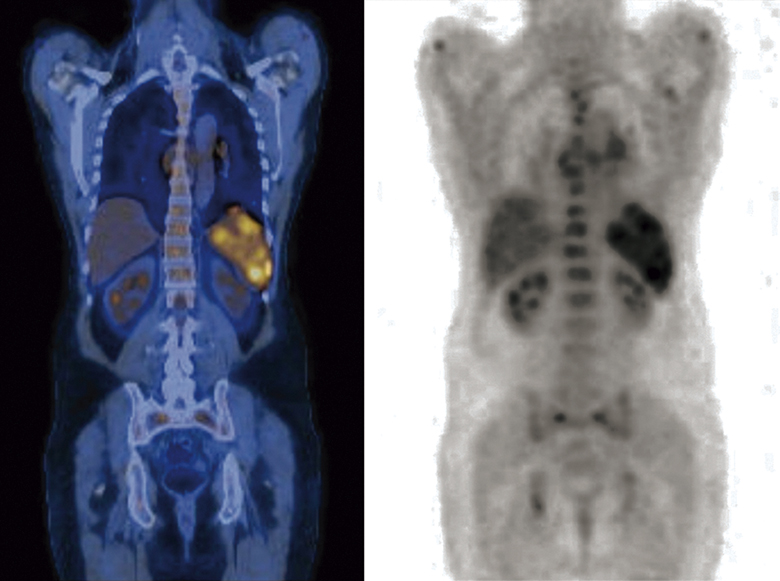

Duas técnicas de Medicina Nuclear podem ser utilizadas na avaliação da sarcoidose cardíaca: a tomografia por emissão de pósitrons com 18F-fluorodesoxiglicose (FDG-PET) e a cintilografia cardíaca com gálio-67. Dentre eles, o exame de FDG-PET tem maior acurácia e se configura, atualmente, como o método de escolha nesse contexto.

O estudo de FDG-PET consegue detectar atividade inflamatória por meio da redução da glicose pelas células inflamatórias dos granulomas sarcoidóticos. Além disso, a cintilografia de perfusão miocárdica fornece informações sobre a fibrose associada à infiltração granulomatosa.

Para garantir a especificidade, o paciente é submetido a um preparo dietético com o objetivo de suprimir a captação fisiológica do miocárdio, o que permite melhor contraste entre o tecido inflamado e o tecido normal. A coleta focal ou focal sobreposta à difusão de FDG no miocárdio é sugestiva de inflamação ativa, enquanto a ausência de coleta sugere ausência de atividade inflamatória significativa ou sucesso terapêutico.

Vale assinalar que a associação de FDG-PET com a perfusão miocárdica com o uso de agentes como o rubídio-82 (pouco disponível em nosso meio) ou 99mTc-sestamibi melhora a acurácia diagnóstica. O padrão de discordância (mismatch) entre áreas de hipoperfusão e captação de FDG indica processo inflamatório ativo (sarcoidose ativa), enquanto o padrão de correspondência (match) pode apontar fibrose miocárdica.